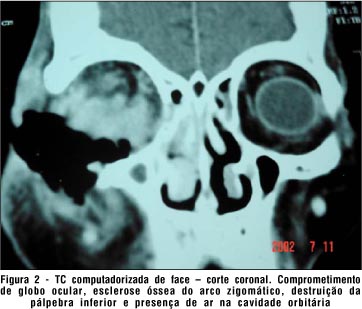

A tomografia computadorizada de crânio e órbitas mostrou extensa lesão ulcerada, profunda, localizada no assoalho orbitário direito, com acentuado acometimento das estruturas intra-orbitárias adjacentes; importante destruição do globo ocular; esclerose óssea do arco zigomático; espessamento mucoso do seio maxilar, células etmoidais, fossas nasais e conchas nasais à direita. Havia solução de continuidade na lâmina papirácea direita. Não havia sinais de extensão intracraniana (Fig. 2 e 3).